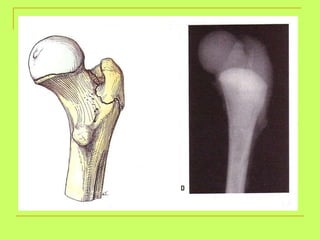

Age from lower limb examination 1) Lesser trochanter  (16y )-----Greater trochanter  (17y)  ------ Head of the femur  (18y). 2) Lower end of the femur + shaft  (21y). 3) Upper end of the tibia +shaft  (21y). 4) Lower end of the tibia +shaft  (18 y).   By foot examination ossific center appears at calcanium at  6 years  and union of epiphysis at the calcanium at  14 years  ,so examining only this bone gives us a range of 8 years

What is the age ? >18 years (united head of femur)

What is the age? above18ys